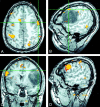

Fig 3.

Images falsely suggesting strong right-hemisphere dominance. A–C, Axial (A), sagittal (B), and coronal (C) SPGR fMR images show minimal left-frontal language activity (crosshairs) during a word-generation task. C and D, Coronal (C) and sagittal (D) fMR images show robust activity in the right IFG and inferior frontal sulcus that falsely implies right-hemisphere language dominance in this individual.